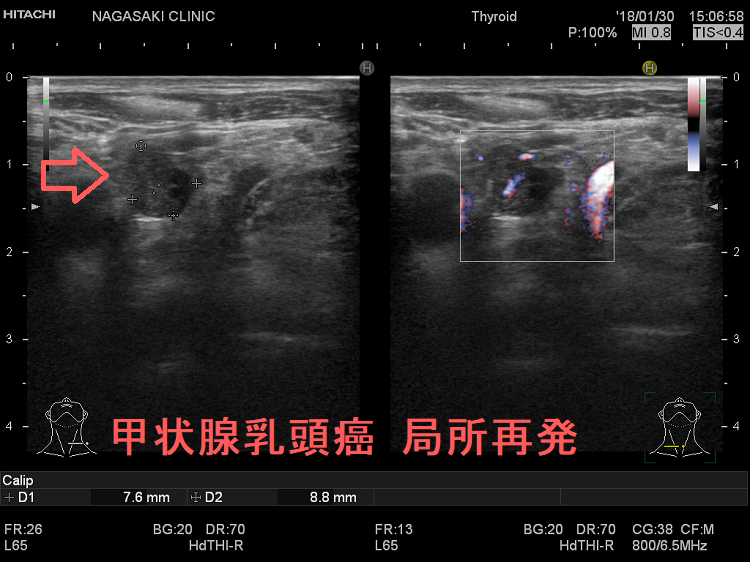

甲状腺乳頭癌の局所再発

甲状腺乳頭癌局所再発 超音波(エコー)画像

甲状腺乳頭癌局所再発 超音波(エコー)画像;いびつな形で、のう胞変性(嚢胞変性)もおこしている。